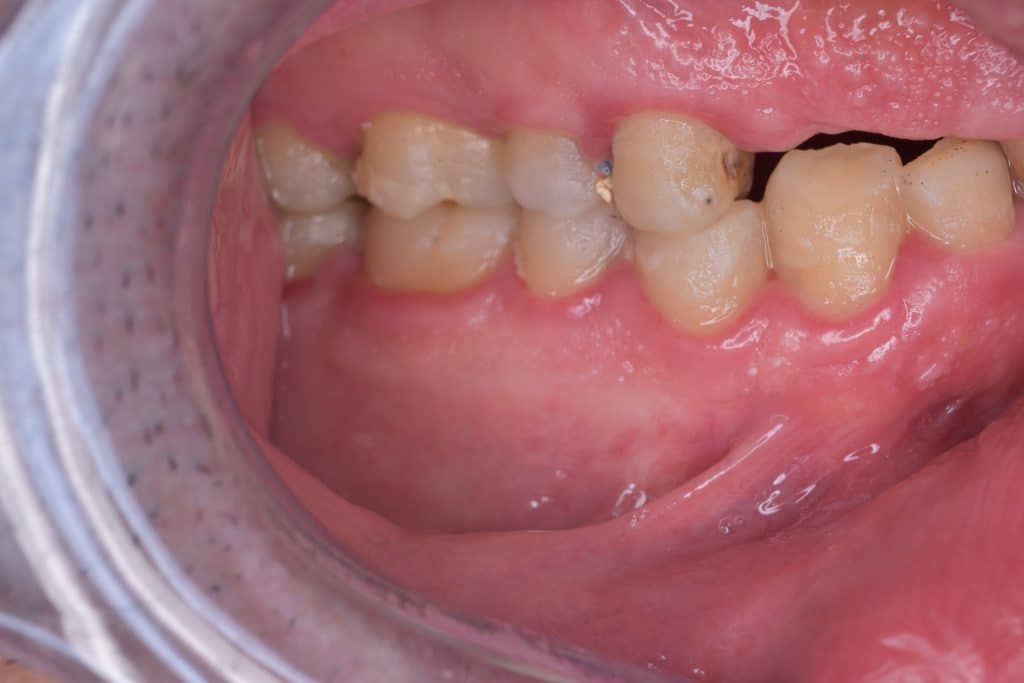

after clinical examination found out :

– loss off VOD ( Vertical Occlusal Dimension)

– attrition in the lowers especially the anteriors

– caries in abutments

– bad oral hygiene